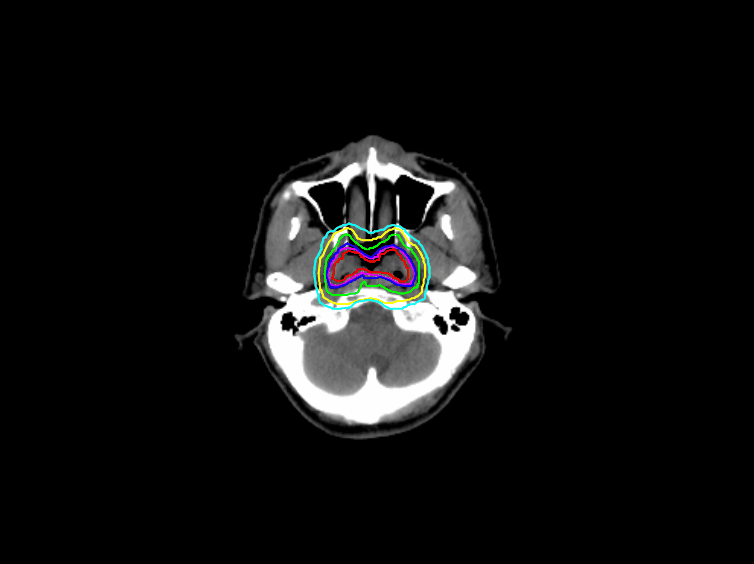

柏視醫(yī)療的IRCS,則能幫助醫(yī)師快速危及器官(OARs)、腫瘤靶區(qū)(GTV)和臨床靶區(qū)(CTV)的勾畫,將其從這項重復(fù)性高而又費時費力的工作中解放出來,以便開展其他關(guān)于腫瘤放療的研究工作。

(IRCS自動勾畫示意圖)

IRCS運用卷積神經(jīng)網(wǎng)絡(luò),并綜合多種圖像處理技術(shù),在小批量數(shù)據(jù)下訓(xùn)練出可靠的器官分割算法,可以自動分割腫瘤與非腫瘤組織,精確勾勒放療靶區(qū),醫(yī)生所需的工作便是對勾畫后的影像進行審核,微調(diào)和修改,大大減少了工作量。同時經(jīng)過資深醫(yī)師審核的自動勾畫影像也可以給年輕醫(yī)生提供參考,減少他們的出錯概率,實時地幫助醫(yī)生提高靶區(qū)勾畫的準確度。